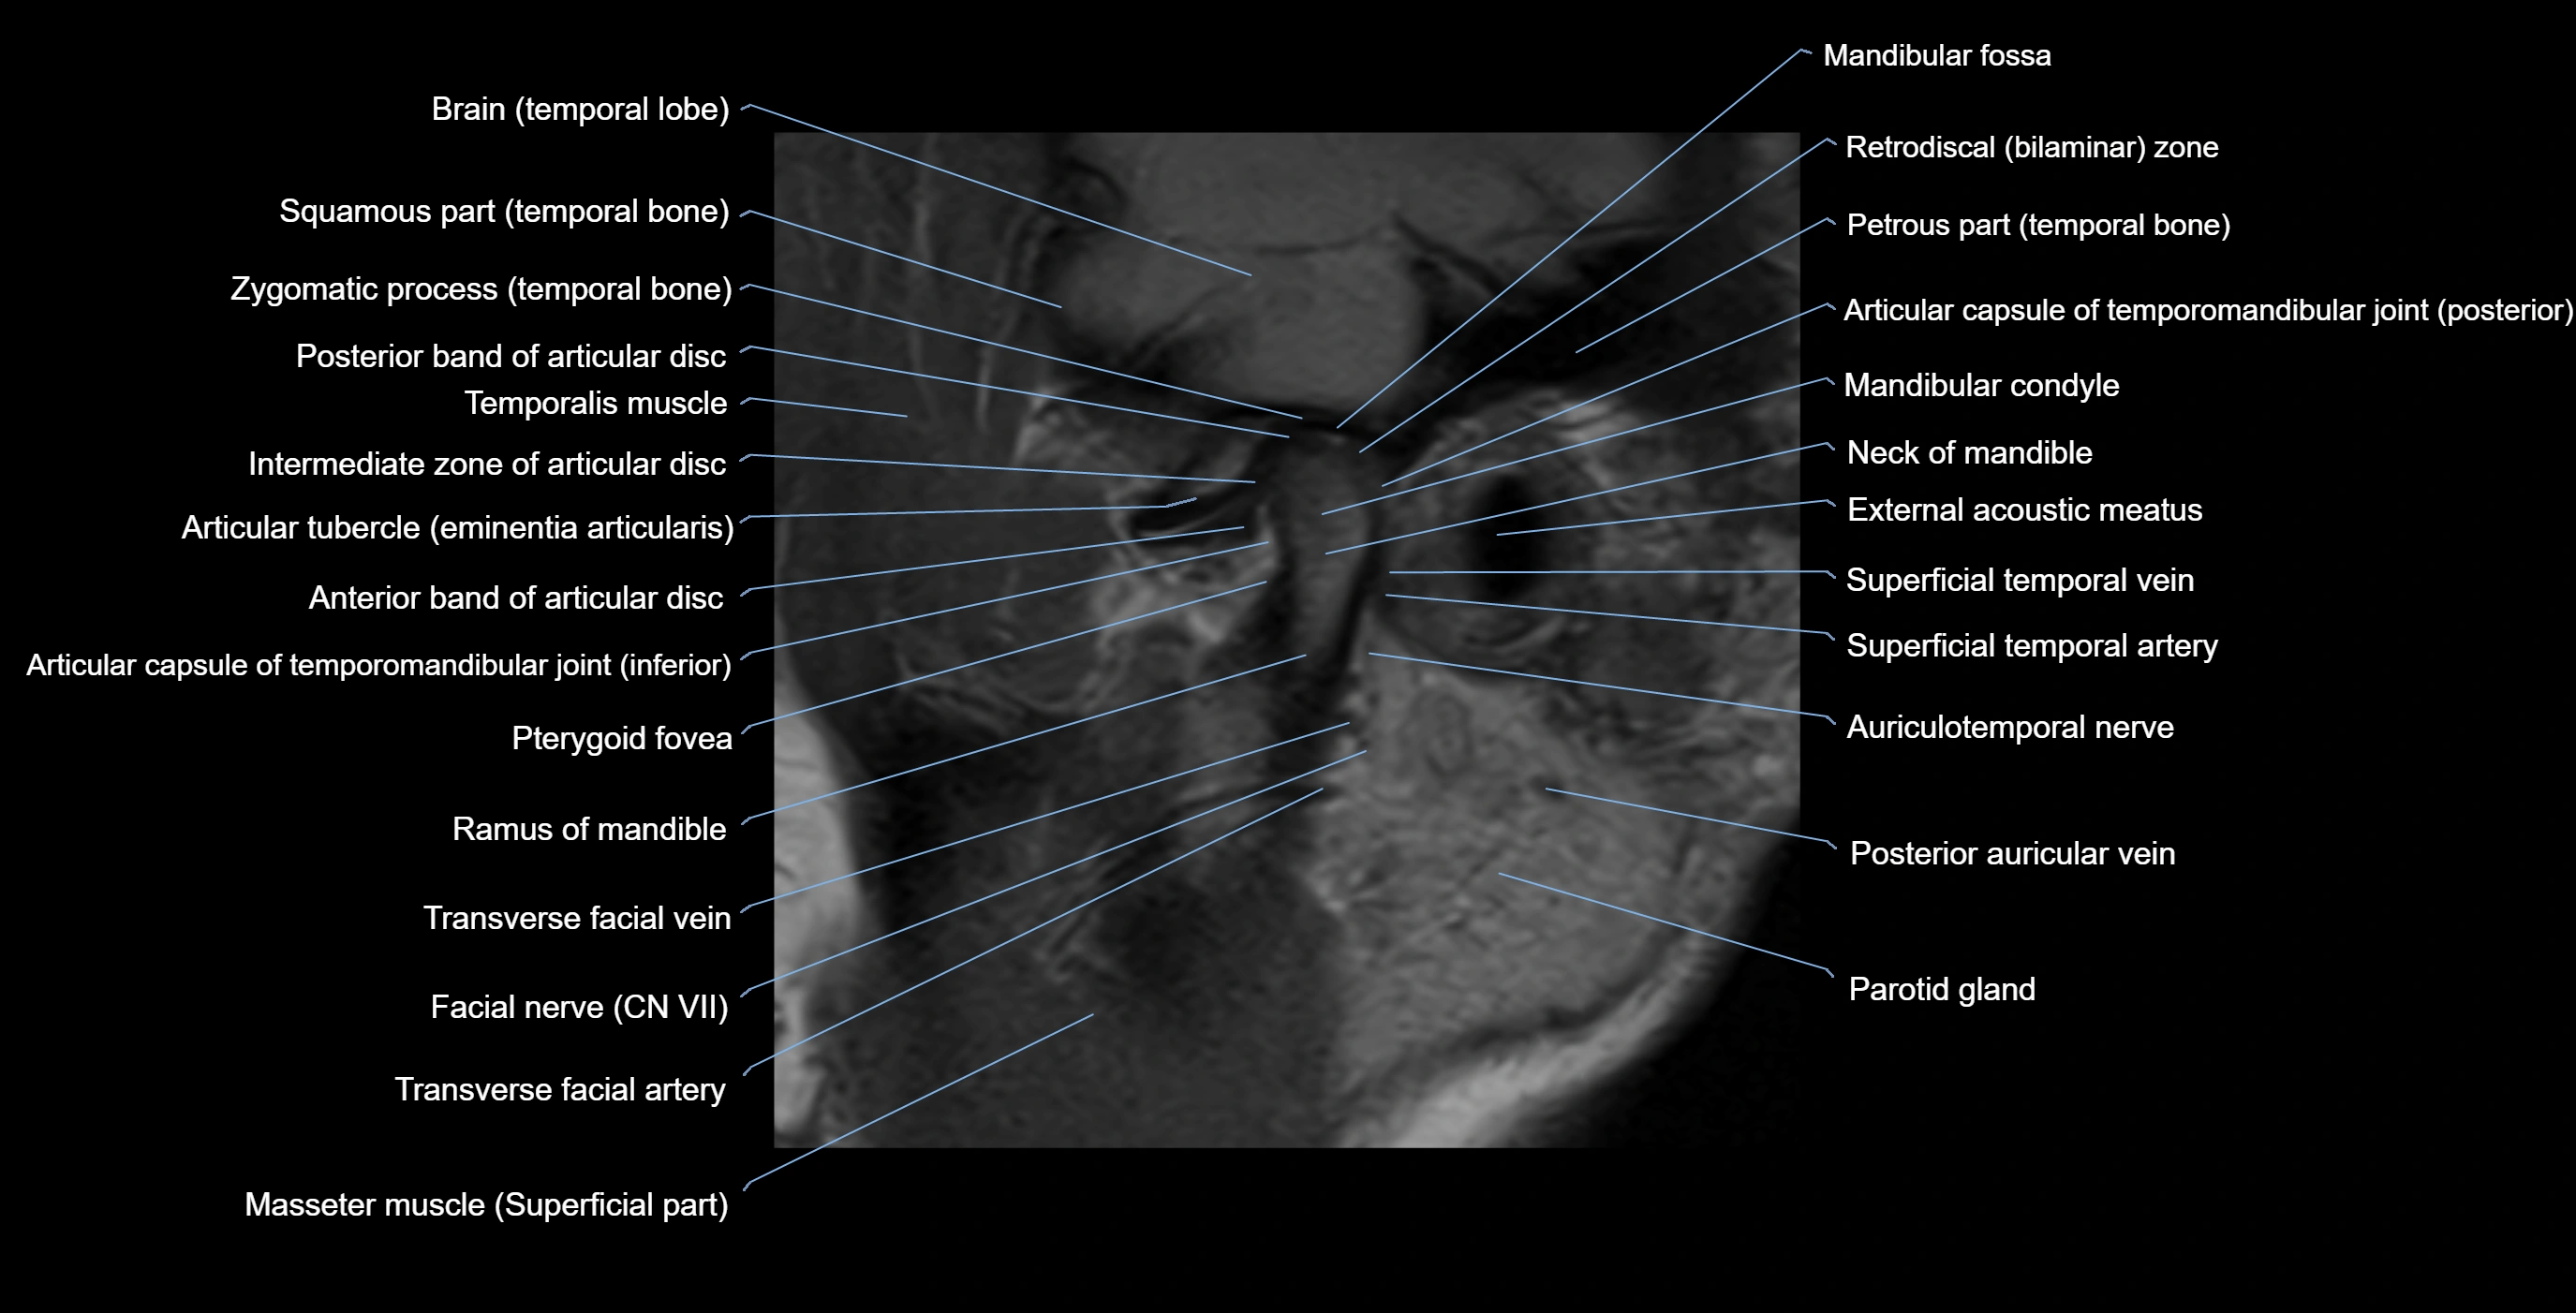

MRI appearance

T1-weighted images:

• Cortical bone: Low signal intensity

• Cancellous marrow: Intermediate to high signal depending on fatty content

• Teeth: Signal void structures

• Adjacent soft tissues: Normal gingiva and oral mucosa signal

T2-weighted images:

• Cortical bone and teeth: Low signal

• Marrow: Intermediate signal